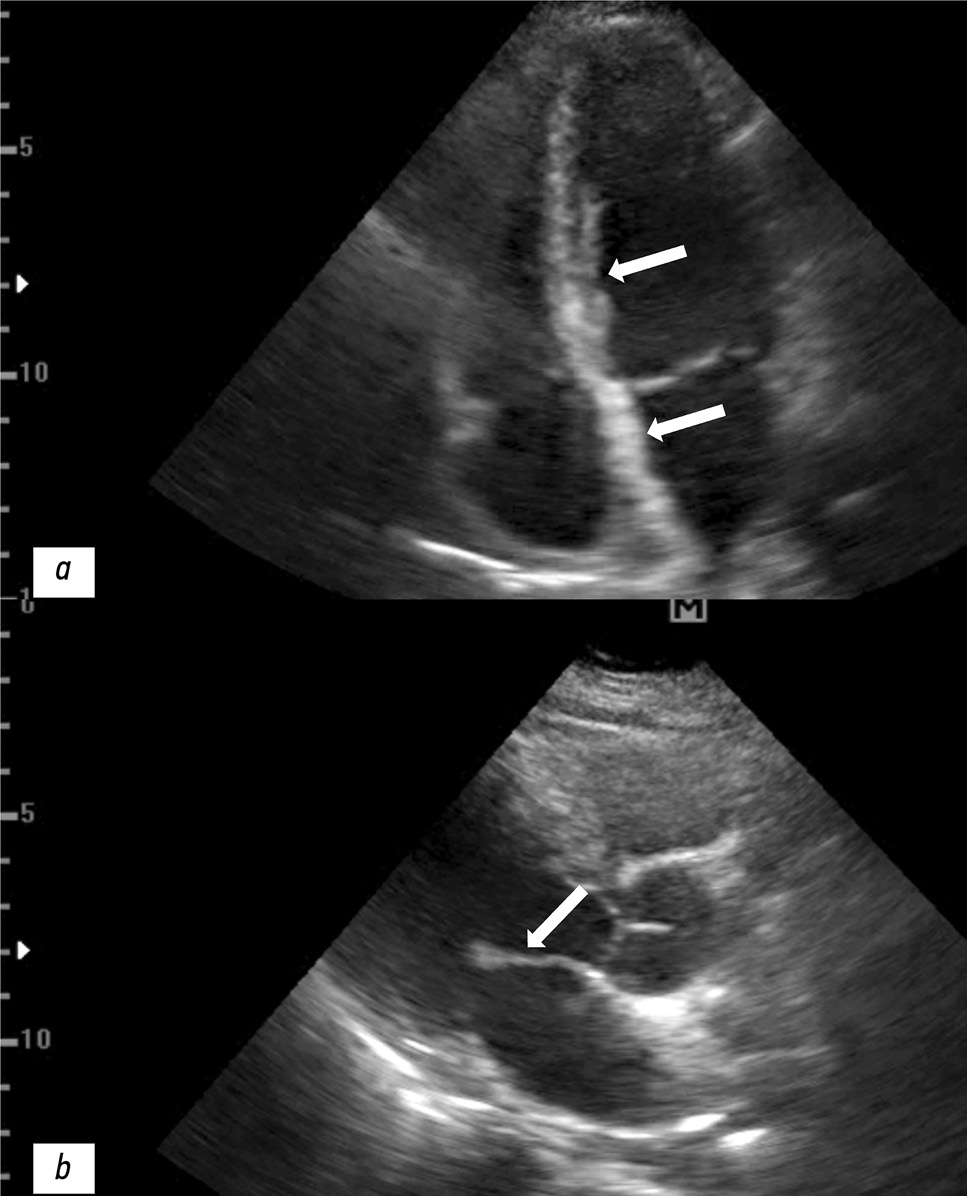

- митральная и трикуспидальная регургитация I степени (рис. 2).

Рис. 2. Результаты эхокардиография пациентки: a — утолщение межжелудочковой и межпредсердной перегородки (белые стрелки); b — утолщение передней створки митрального клапана (белая стрелка).